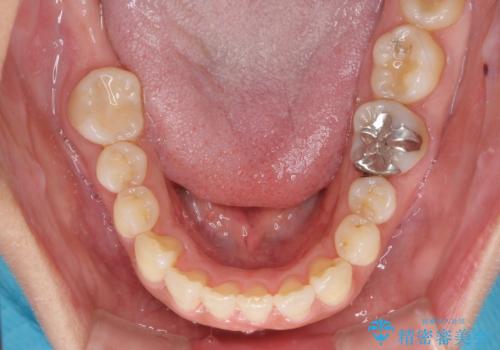

軽度な歯列不正 インビザライン・ライトによる矯正治療

- 上下前歯の叢生を気にして来院された患者様です。

費用を抑え、期間もあまりかけずに治療をしたいとのことで、インビザライン・ライトを用いて矯正治療を行うこととしました。